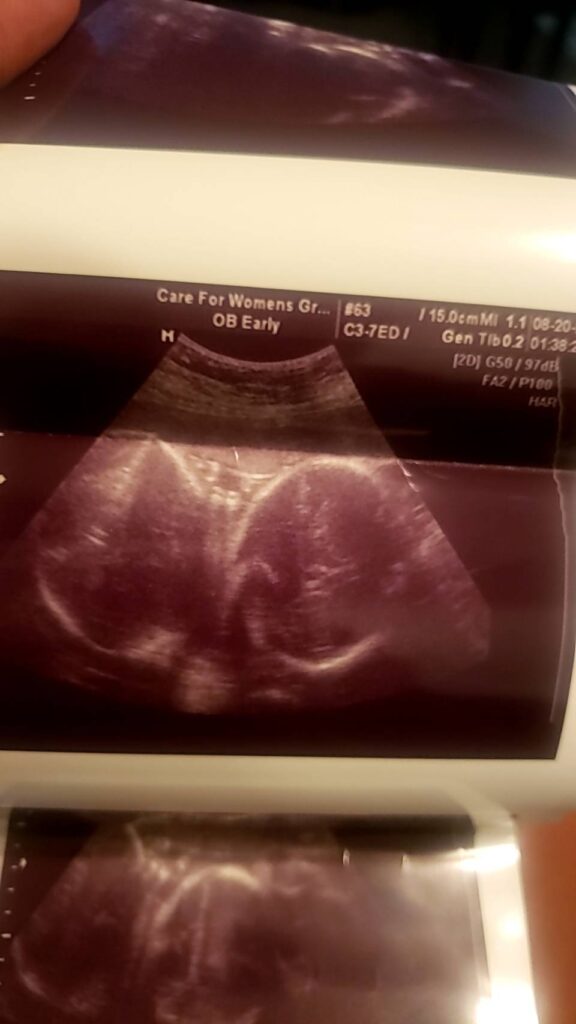

雙胞胎超音波紀錄 : 27週 Posted on August 25, 2020 by yourtesttubebaby 27週的雙胞胎寶寶就是長這樣的! 哇,再十週就要報到啦!!!🎉🎉🎉 ↑↑↑(圖一) 照出其中一位寶寶的臉與眼睛 ↑↑↑(圖二) 兩個寶寶頭與頭相靠相依 ☀ 網站上每位小寶貝都是我們的成功案例,照片皆經父母親許可使用 ( 若未經允許請勿轉載 ) ☀ Posted in Uncategorized